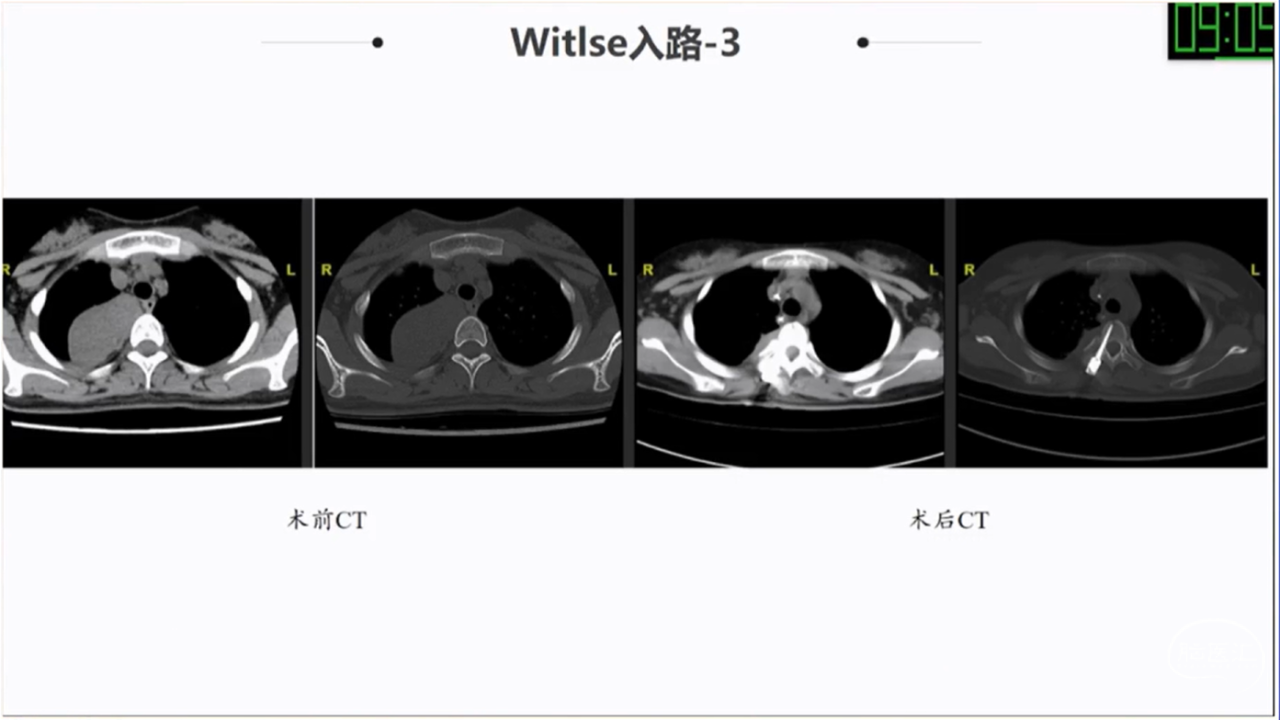

椎旁肿瘤种类多样,手术切除是主要的治疗方法;血供一般,病灶内切除减容,为肿瘤的全部切除提供有利条件;Witlse入路治疗椎旁巨大肿瘤优势明显;椎体破坏、血管侵犯、胸膜下的病例尽量选用经胸入路或者联合入路。

· Witlse入路治疗椎旁巨大肿瘤优势明显